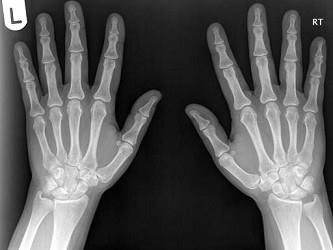

男,请根据其正常手的影像图像,判断其最可能的年龄 ( )A、76岁左右B、56岁左右C、26岁左右D、36岁左右E、16岁左右

问题 男,请根据其正常手的影像图像,判断其最可能的年龄 ( )

选项 A、76岁左右 B、56岁左右 C、26岁左右 D、36岁左右 E、16岁左右

答案 B